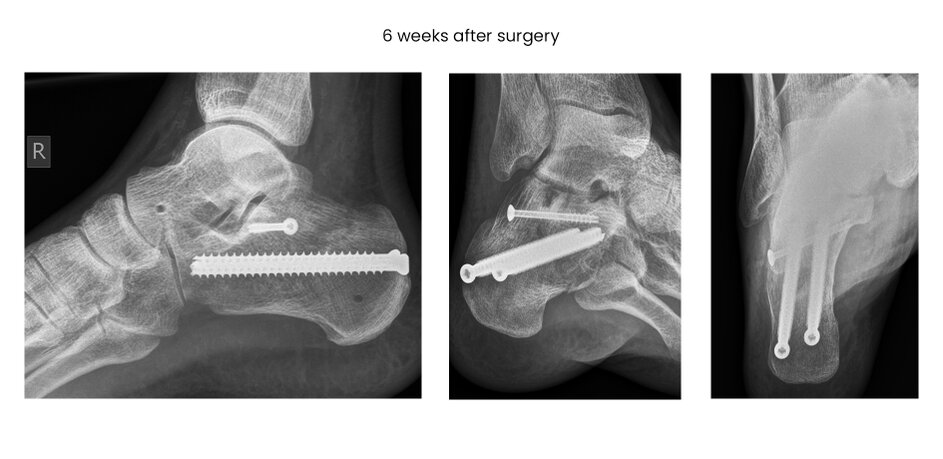

case 15FM, 34y, male, depression-type, surgery on 2nd day after trauma, chain smoker